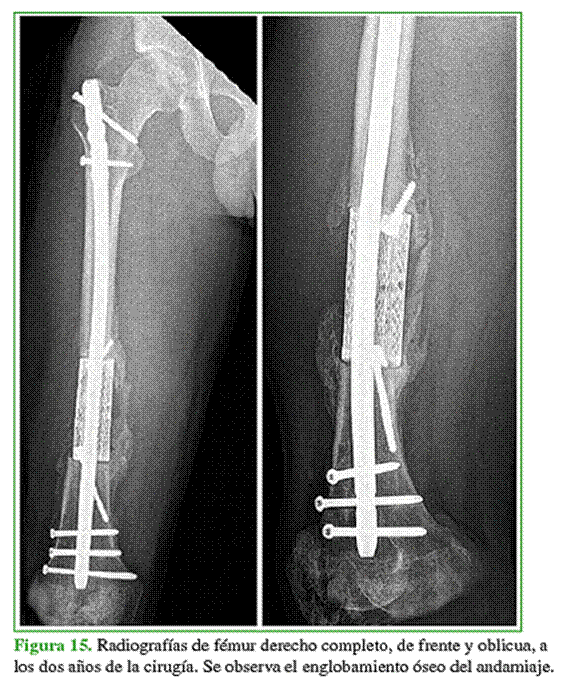

Antes de la cirugía definitiva, se colocaron un enclavado endomedular para igualar la longitud del miembro y un espaciador de cemento con vancomicina-gentamicina; se administró tratamiento antibiótico por vía oral (Figura 14). A los cuatro meses, se procedió al recambio del espaciador con toma de muestras, que fueron negativas. A las dos semanas, se realizó la cirugía reconstructiva (Figura 15).

A los 150 días, se confirma la incorporación ósea completa mediante tomografía computarizada en todos los pacientes. Asimismo, en las radiografías simples, se observa el “englobamiento” óseo del implante, que se considera secundario a la cualidad inductora y la calcificación parcial de la membrana.